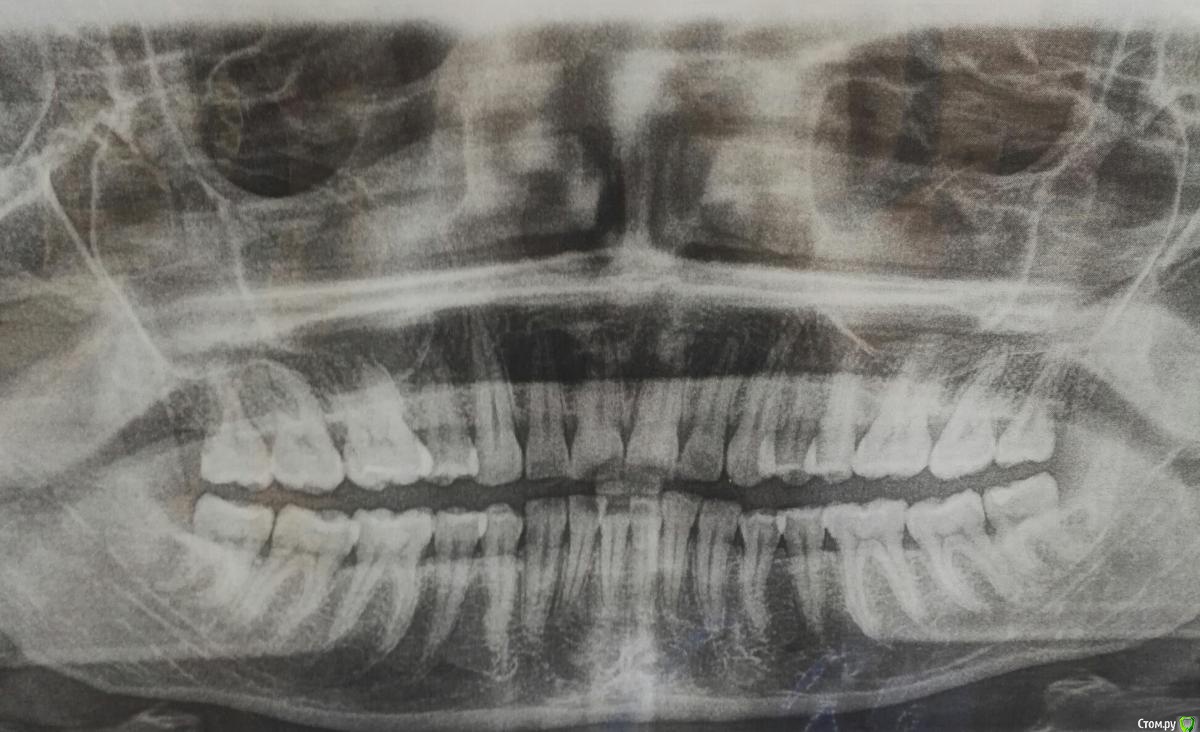

Izmailla Опубликовано 24 июля, 2017 Автор Поделиться Опубликовано 24 июля, 2017 (изменено) Прилагаю снимки, сделанные сегодня. Пожалуйста, подскажите, что думаете? Первый ортодонт, у которого я была говорит, что в бс нет смысла, центр поставить невозможно, при удалении четвёрки слева вч станет меньше, что повлечет удаление четвёрок на нч, а в результате все в общем будет плохо) Изменено 24 июля, 2017 пользователем Izmailla Ссылка на комментарий

Izmailla Опубликовано 24 июля, 2017 Автор Поделиться Опубликовано 24 июля, 2017 Ещё фото Ссылка на комментарий

Brigita Опубликовано 24 июля, 2017 Поделиться Опубликовано 24 июля, 2017 Есть еще один вариант - раздвинуть справа под имплантат - вернуть все на свои места. Верхние восьмерки нужно будет удалить. 1 Ссылка на комментарий